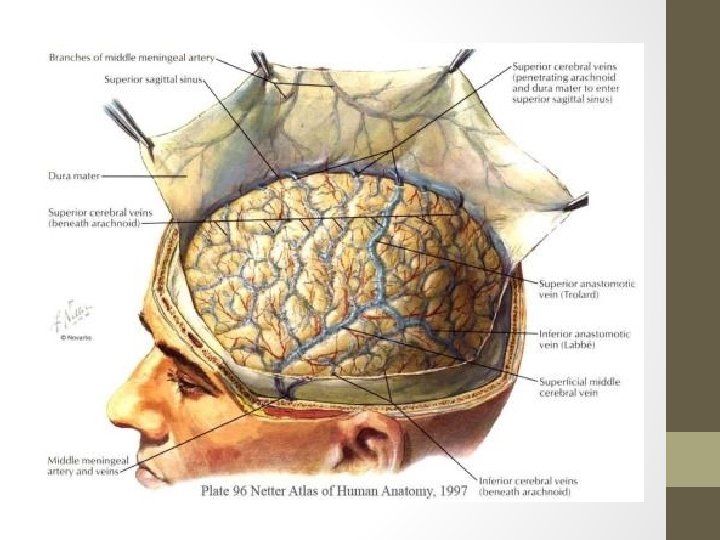

• The cerebral veins drain the brain parenchyma and are located in the subarachnoid space. They pierce the meninges and drain further into the cranial venous sinuses. • The cerebral veins lack muscular tissue and valves. -superficial (cortical) cerebral veins -deep (subependymal) cerebral veins

Superficial Venous System • Comprised of the sagittal sinuses and cortical veins. • The cortical veins course along the cortical sulci, drain the cortex and some of the adjacent white matter. • Can be subdivided into superior, middle and inferior groups. • Important veins of superficial cerebral venous system; -Superficial middle cerebral vein -Superior anastomotic vein of Trolard -Vein of Labbé